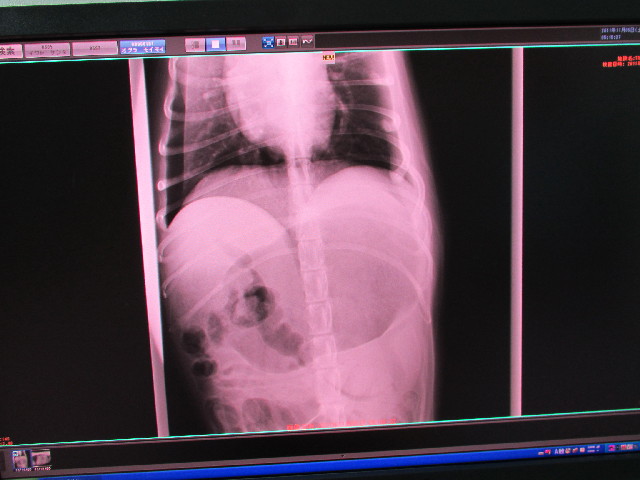

レントゲンでわかるは“胃が満腹の時くらい大きく”なっていてガスがたまっている(鼓張/胃拡張の初期?)だが、ガスは十二指腸などに流れているので自分で出そうとはしているとのこと。

※胃拡張になってしまうと、ガスが充満してさらに倍くらい大きくなり、胃にくっついている臓器の重さでひっくり返って胃捻転にってしまうそうで、胃捻転は即刻処置しないと命にかかわります。

翌日かかりつけの獣医さんに行って救急でのレントゲン等を診てもらったところ、もいは鼓張だけど思ったよりも胃が膨らんでしまっているわけではないので大丈夫そうだねとのことでした。